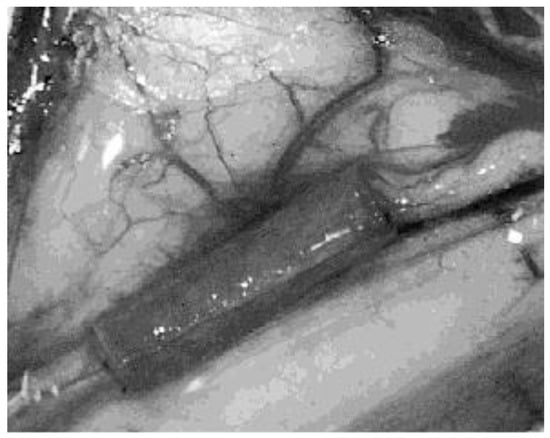

| Kalbermatten et al., 2008a [22] | Sciatic (mixed)/10 mm/2 weeks | Rats (24) | Poly-3-hydroxybutyrate (PHB) (molecular weight 150 KDa) | PHB sheets rolled (16 G) 14 mm long, 2 mm diameter | A fibrinogen-cell solution was made in 1:10 dilution from Tisseel® containing 9 mg/mL fibrinogen and 80 × 106 Schwann cells/mL. This solution (25 mL) was used to coat PHB that was treated with 25 mL of diluted thrombin solution (5 IU/mL) for 10 min. | Histology, IHC, macroscopic morphology | Beneficial combinatory effect of an optimized matrix, cells and conduit material (PHB) as a step towards bridging nerve gaps. |